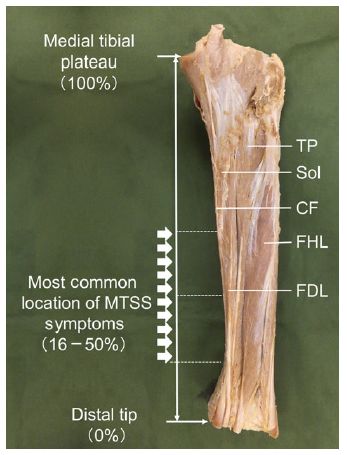

Edama M, Onishi H, Kubo M, Takabayashi T, Yokoyama E, Inai T, Watanabe H, Nashimoto S, Koga Y, Kageyama I. Gender differences of muscle and crural fascia origins in relation to the occurrence of medial tibial stress syndrome. Scandinavian Journal of Medicine & Science in Sports. 2015; DOI: 10.1111/sms.12639.